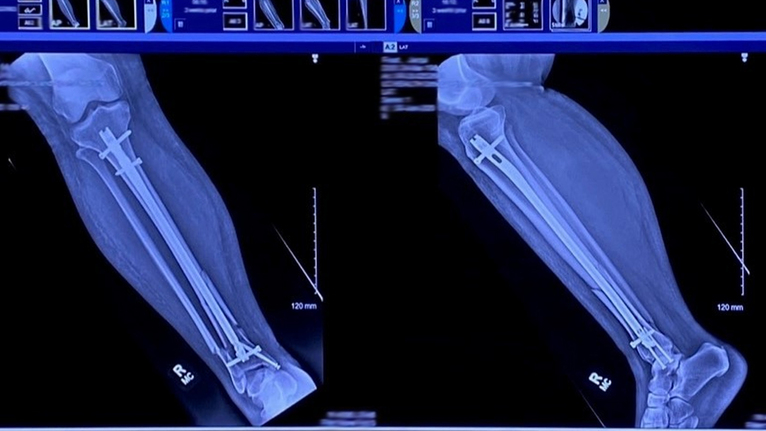

“Jacqui’s injury was severe because not only was it a break at her ankle that needed surgery, but she also broke her tibia which made her leg unstable,” Dr. Dixon explained. “She required a nail that was placed inside her tibia to fix the leg, and then plates and screws to stabilize her ankle.”

Physically, Jacqui was prohibited from bearing any weight on her leg for six weeks. Her world essentially turned upside down, as she quickly transitioned from being an independent mom, to having to rely on her husband and kids for what felt like everything.